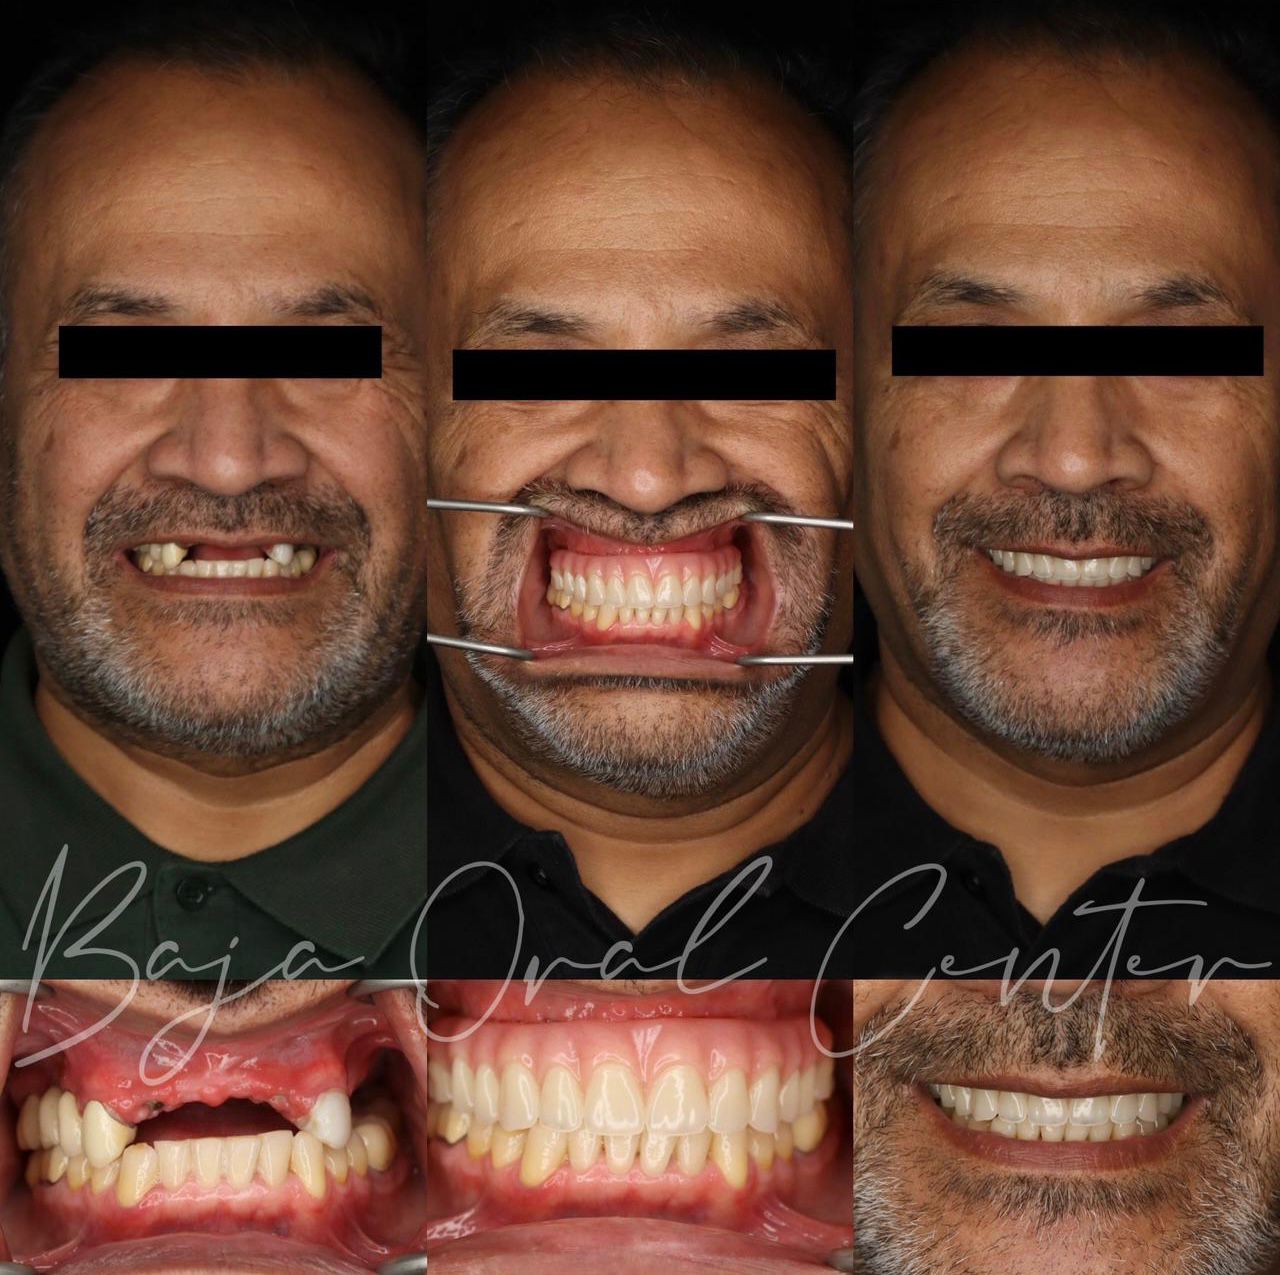

Start your smile transformation in just one trip to Tijuana. Your first phase includes extractions, 4 dental implants per arch, and fixed temporary teeth — all in one day. After 4–6 months of healing, you’ll return for your custom zirconia prosthesis for just $4,000.

Not all smiles need the same solution. That’s why we master every technique

All on 4

•All-on-4 or All-on-6 for stable, proven solutions when there’s an ideal jaw bone.

Phase 1: All on 4 — $7,850

What’s included?

✅ Complete diagnostics & personalized planning (CBCT + records)

✅ Expert placement of 4 implants

✅ Fixed temporary teeth in 72 hours so you can smile & eat right away

✅ Post-op medications & easy recovery support

Phase 2: all in 4 — $4,000

✅ Custom zirconia or premium hybrid final teeth for a perfect, natural look

✅ 5 Year warranty

We proudly showcase the positive experiences of patients who have undergone a full arch rehabilitation with traditional / Corticobasal Implants with Full Arch Baja